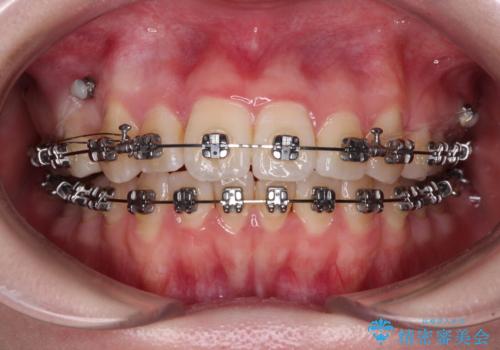

【モニター】八重歯を片側の抜歯矯正で治す メタルブラケット装置

- 八重歯とずれた正中を気にして来院された患者様です。

非抜歯矯正ではデコボコを解消することでより口元が突出する可能性があるため、上顎右右側の小臼歯1本の抜歯を行い、ワイヤー装置による矯正治療を行うこととしました。

正中位置を合わせるために、上顎臼歯部にアンカースクリューを埋入することとしました。

お仕事の予定を調整しやすく、平日の昼の時間帯に通院可能であったので、非常にスムーズに治療を進めることができ、1年半で無事に治療を終えることができました。